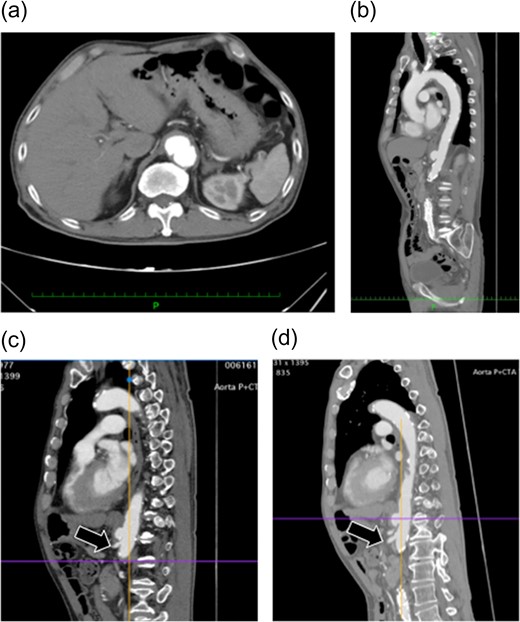

(a and b) Preoperative contrast-eCT. (c and d) eCT performed on postoperative day 13. A cyst is seen on the pancreatic tail (black arrow), while no contrast effect is seen in the spleen (white arrow). (e and f) CT performed on postoperative day 21. The pancreatic cyst has started to shrink. Part of the spleen becoming necrotic does not conflict with an etiology of ischemia due to embolization of the splenic artery.

The patient did not have preoperative risk factors for pancreatitis. Additionally, CT images taken at the arterial and late phases (180 s) did not show a contrast effect in the splenic artery distal to the embolism or the spleen. Pancreatitis occurred immediately after the arteries perfusing the pancreas were surgically embolized. Therefore, we diagnosed pancreatitis due to reduced pancreatic blood flow secondary to embolization (Fig. 2).

We confirmed the collateral pathways on preoperative CT, and imaged the SMA intraoperatively before embolizing the celiac artery, confirming communication between the branches (Fig. 2). Nevertheless, pancreatic ischemia occurred. This patient's collateral pathway through the dorsal splenic artery was considered insufficient to perfuse the pancreatic tail and spleen. Additionally, this patient had a history of endovascular aortic repair. It is possible that this previous procedure could have had adverse effects on the perfusion of the celiac artery via the SMA. If we had performed SMA arteriography at the beginning of the surgery with the celiac artery occluded by balloon, we may have been able to predict and avoid these phenomena. We should consider carefully which arteries to be embolized.